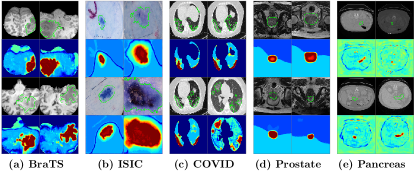

Refer to caption

Figure 1: Visualization of the input images with object masks (a) and three corresponding deep features (b)-(d) extracted from three convolutional units. (b) shows that the activated values are on the background pixels/voxels, (c) shows the activated values are on the object pixels/voxels and (d) shows the activated values are on both object and background pixels/voxels.

Fig. 1(b)-(d) give examples of three deep feature maps extracted on different units of convolutional layers on the trained neural networks from the input images (as shown in Fig. 1(a) with the ground-truth object masks shown in red). We show that features with the high activated value on the background pixels/voxels (Fig. 1(b)), on the object pixels/voxels (Fig. 1(c)) and on both the object and background pixel/voxels (Fig. 1(d)). The activated values (as measured by the CAM [31]) for objects are only high in Fig. 1(c). However, the aim of segmentation is to separate the object and background pixels/voxels in the input images. Thus, the feature maps on Fig. 1(b) are also discriminative since the object regions (with small responses) can be separated from the background regions (with large responses). In fact, a negative weight can be applied on feature maps on Fig. 1(b) to highlight the object regions in the subsequent layers. Therefore, the activated values in feature maps do not necessarily translate into the ability for segmentation but the segmentation ability of deep features is important for the final segmentation.

Another observation from Fig. 1 is that the segmentation abilities of the deep features from different units are different. For example, the segmentation abilities of the feature map shown on Fig. 1(b) and Fig. 1(c) are greater than the segmentation abilities of the feature map shown on Fig. 1(d). In general, the segmentation abilities of deep features on different layers or on different units from the same layer are different and quantifying the segmentation abilities is important to understand the deep features and further understand the whole neural network for medical image segmentation.